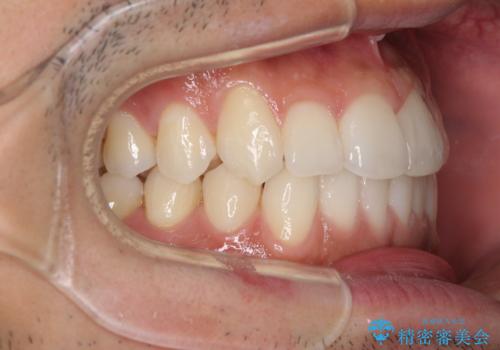

前歯のデコボコを治したい インビザライン矯正治療

- 前歯のデコボコを治したいとのことで来院された患者様です。

上下顎ともに歯列全体の後方移動とIPR(歯と歯の間を削る)によってデコボコが解消するように設計し、インビザラインにより治療を行うこととしました。

毎日22時間以上しっかりとマウスピースを装着していただいたので、スムーズに治療が進みました。歯と歯の間を削ることでうまくスペースコントロールでき、1年強で終えることができました。